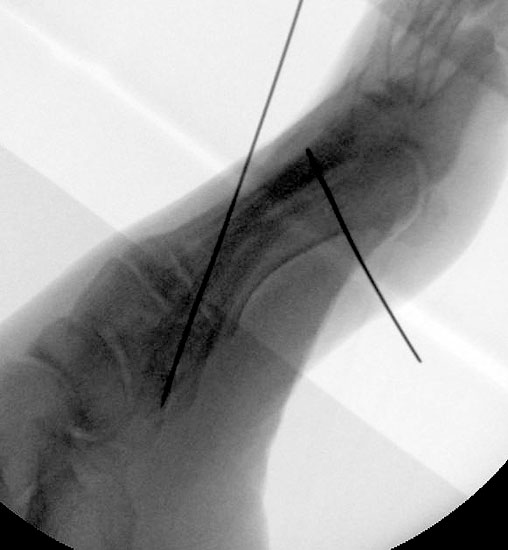

Röntgenaufnahme des Fußes im Stehen im dorsoplantaren und seitlichen Strahlengang (Abb. 1a-b).

Abbildung 1a

Abbildung 1b